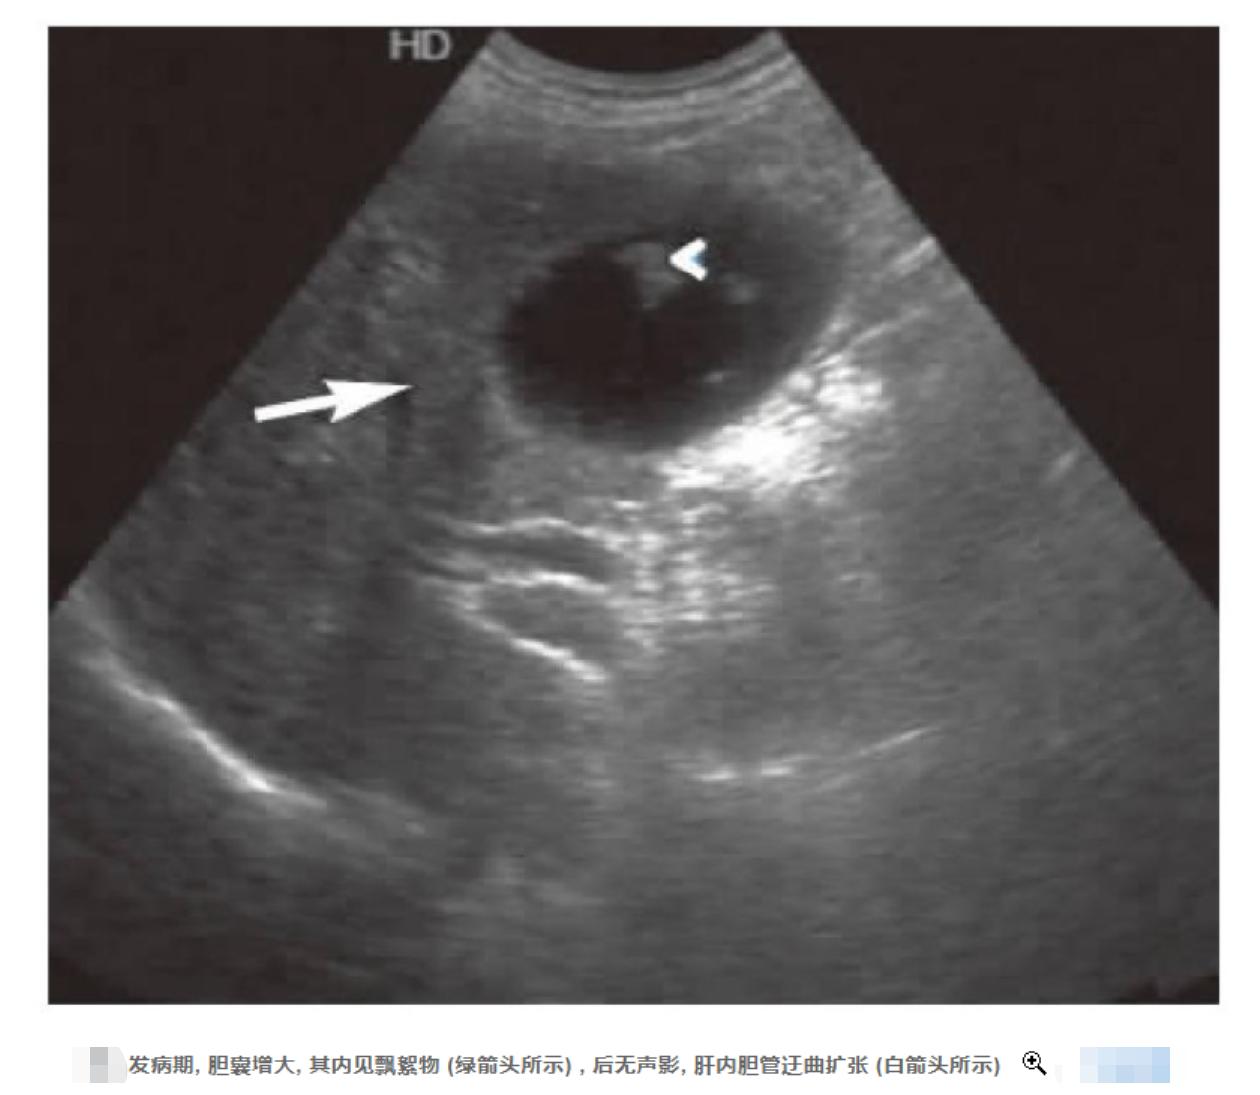

很可能病灶所在就是在肝脏,于是医生开出了 CT检查以及B超检查 。这两项检查都发现,他的肝脏有些增大,而且有胆囊炎和胆管炎,胆内还有小囊性病变。